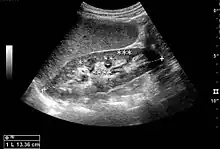

![]() Doppler ultrasound (US) of a normal adult kidney with the estimation of the systolic velocity (Vs), the diastolic velocity (Vd), acceleration time (AoAT), systolic acceleration (Ao Accel) and resistive index (RI). Red and blue colors in the color box represent flow towards and away from the transducer, respectively. The specrogram below the B-mode image shows flow velocity (m/s) against time (s) obtained within the range gate. The small flash icons on the spectrogram represent initiation of the flow measurement.[1] | |

Doppler ultrasonography of the kidney is widely used, and the vessels are easily depicted by the color Doppler technique in order to evaluate perfusion. Applying spectral Doppler to the renal artery and selected interlobular arteries, peak systolic velocities, resistive index, and acceleration curves can be estimated (Figure 4) (e.g., peak systolic velocity of the renal artery above 180 cm/s is a predictor of renal artery stenosis of more than 60%, and a resistive index, which is a calculated from peak systolic and end systolic velocity, above 0.70 is indicative of abnormal renovascular resistance).[1]